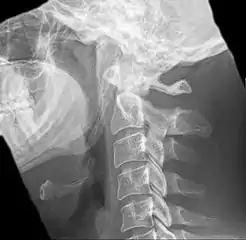

| Anteroposterior and lateral radiographs of cervical spine showing ossification of the stylohyoid ligament on both sides | |

Radiograph, lateral view showing elongated stylohyoid process and stylohyoid ligament ossification

Radiograph, lateral view showing joint-like formation in ossified stylohyoid ligament

Imaging is important and is diagnostic. Visualizing the styloid process on a CT scan with 3D reconstruction is the suggested imaging technique.[12] The enlarged styloid may be visible on an orthopantogram or a lateral soft tissue X ray of the neck.